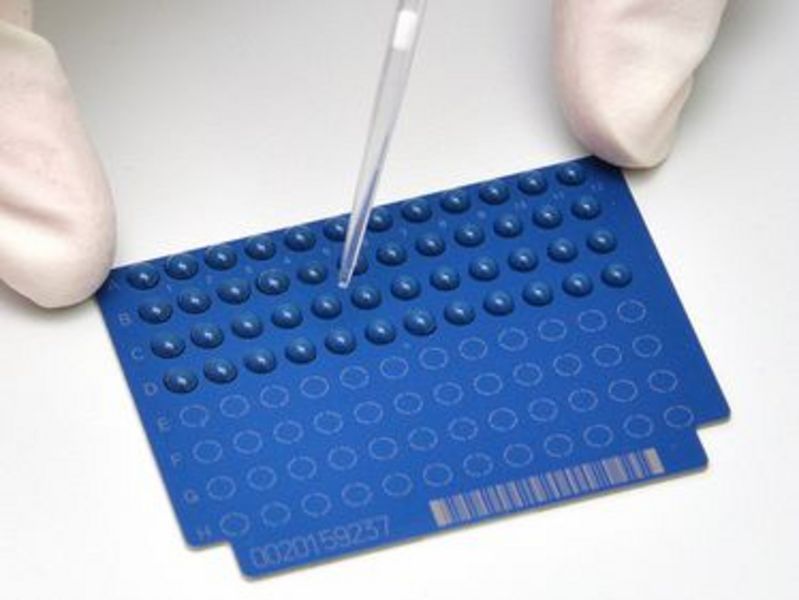

Schneller ist besser: Mikrobiologen entwickeln Methode zur beschleunigten Bestimmung von Antibiotikaresistenzen

Schneller ist besser: Mikrobiologen entwickeln Methode zur beschleunigten Bestimmung von Antibiotikaresistenzen